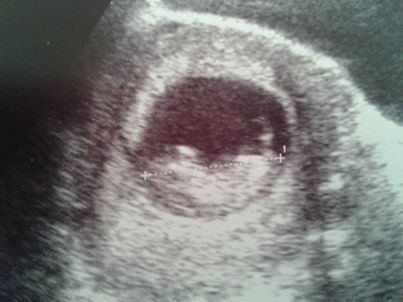

hoping this has attached ok. this is my wee bubs at 11 weeks. hope the pic is clear enough x